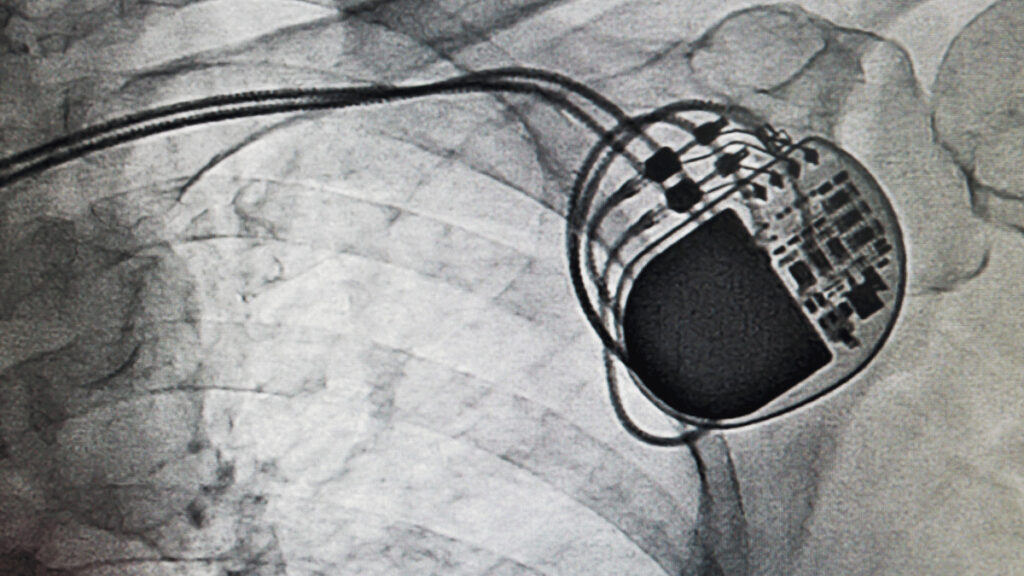

ペースメーカーは、心臓を刺激するリード線を留置し、本体につなげて鎖骨下あたりの胸に埋め込みます。

大きさは機能にもよりますが、直径が4~5㎝のソラマメ型で厚さは5㎜位をイメージしてみてください。